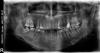

Inning1 Опубликовано 7 апреля, 2013 Поделиться Опубликовано 7 апреля, 2013 Добрый день. Решил обраттьися сюда со своей проблемой.. В мае того года залечили мне верхний зуб,причем перелечивали 2 раза,но в итоге все стало хорошо и зуб перестал меня беспокоить,но в январе начала побаливать еле заметно,если не жевать им,то и не болит,но иногда бывало такое чувство,что кусочек пищи там застревает и "подгнивает"..был характерный вкус,когда трогаешь там,но потом это прошло само собой,пошел в клинику,сделали снимок,оказалось пм выведен за верхушку на 6 мм! Но меня терзают сомнения ведь больше полугода зуб не болел у меня,и как мне кажется побаливает не от выведенного материала ,а там что-то не так с пломбой! Прокомментируйте пожалуйста снимки для начала,может этот зуб нужно просто перелечить? Очень боялся ,что зуб будет болеть в самолете,за это время несколько раз летал,все было нормально! Ссылка на комментарий

Inning1 Опубликовано 7 апреля, 2013 Автор Поделиться Опубликовано 7 апреля, 2013 (изменено) Можно ли говорить о том,что пм находится прямо в пазухе??судя по кт,не похоже..Еще забыл добавить,если вдохнуть воздуха(именно в этот зуб) то чувствуется ,как воздух оникает в него,такое обычно бывает из-за дырки в зубе,но я сужу по себе.. Но дырки вроде как не нашли,а вчера обнаружил небольшую трещину на зубе,если провести ногтем-можно почувствовать!к врачу иду во вторник,предлагают перелечить,но я боюсь,не протолкнется ли пм дальше в процессе перелечивания? Дело в том,что я через неделю улетаю на учебу,буду учиться на летчика и мне все это крайне важно,так как непосредственная близость гайморовой пазухи..очень жду ваших мнений!!! Спасибо! Изменено 7 апреля, 2013 пользователем Inning1 Ссылка на комментарий

IvanK Опубликовано 7 апреля, 2013 Поделиться Опубликовано 7 апреля, 2013 Здравствуйте.Я бы рекомендовал консультацию ортодота. По 26 зубу: необходимо пользоваться зубной нитью.Зубная нить должна "заходить" и "выходить" со щелчком, не рваться, не разволокняться. Если все так - хорошо. В Вашем случае, по моему мнению, показание для закрытия зуба коронкой. По поводу выхода материала: достать его через канал зуба невозможно (пусть меня поправят терапевты, если я ошибаюсь ). Материал в пазухе, воспалительные явления в пазухе - есть. Ссылка на комментарий

IvanK Опубликовано 7 апреля, 2013 Поделиться Опубликовано 7 апреля, 2013 Зубной нитью проверяют хорошо ли сделаны те места зуба, которые контактируют между собой (между зубами). Зубная нить - средство гигиены, как зубная щетка. Пользуясь только щеткой Вы не можете очищать промежутки между зубами, для последних необходима зубная нить.Проблема застревания пищи между зубами - не проблема каналов. Дистальный щечный канал действительно не запломбирован до верхушки. Данный факт может поддерживать воспалительный процесс в пазухе.Убрать вышедший материал можно вместе с зубом, или с помощью ЛОР-Врача (эндоскопически), или комбинируя обоих.по поводу синус -лифтинга - возможно, я так не делал, послушаем мнение коллег.Риск возникновения гайморита - есть, каков? Одному Богу известно когда это может случиться. Ссылка на комментарий

shishok Опубликовано 8 апреля, 2013 Поделиться Опубликовано 8 апреля, 2013 Вам бы ещё неплохо удалить нижний правый восьмой зуб и пролечить кариес на задней поверхности соседней семёрки(или в перспективе потеряете оба). Ссылка на комментарий